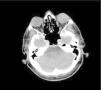

Three years later, he presented with decreased vision in the left eye. Orbital MRI showed tortuosity of the optic nerve and slight widening of the perioptic space (Figure 1). Cranial MRI revealed only age-related changes. Cytology and flow cytometry of vitreous fluid demonstrated CD20 and CD79a positivity with high proliferative activity, consistent with B-cell neoplasia.

PET-CT revealed limited FDG uptake (SUVmax 5.02) in the anterior aspect of the left orbit (Figure 2), with no additional systemic involvement. Based on his disease history, systemic high-dose methotrexate combined with cytarabine and intrathecal therapy was initiated. Radiotherapy was also considered.